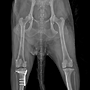

| 양측 골반다발성 골절+ 발목 골절(끊어짐) --교통사고 | 25.03.07 |